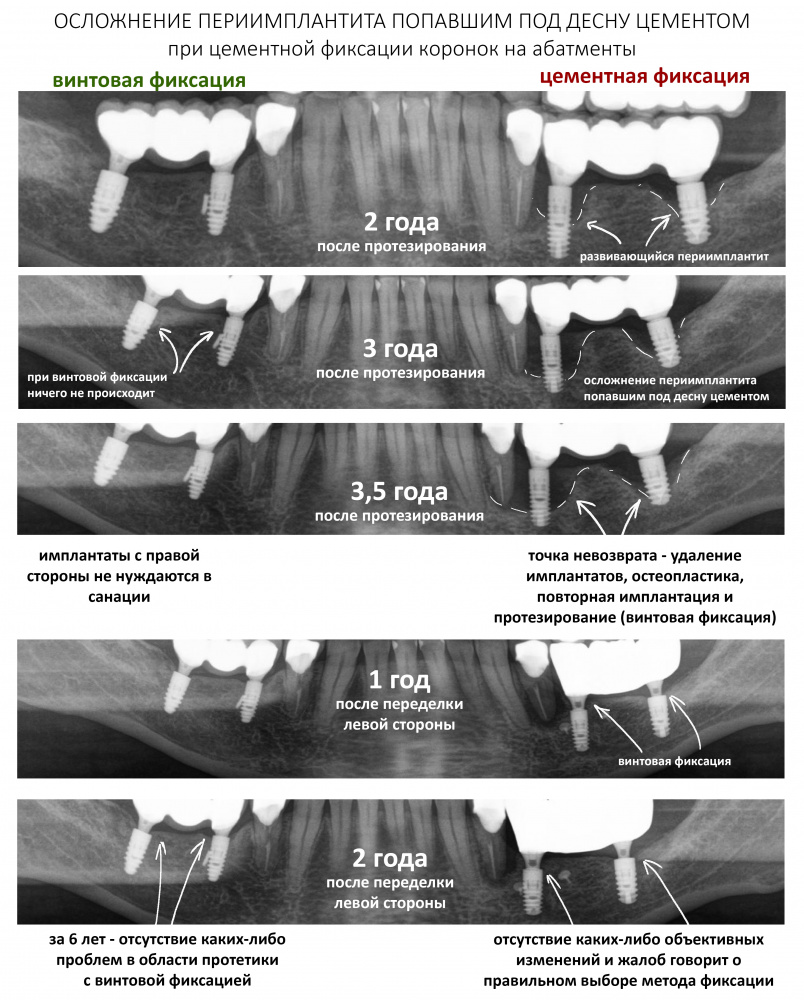

Дополню тезис — сними и выкинь. Как правило, именно рукожопая протетика является причиной ухудшения гигиены, воспаления десны и превращает периимплантит в аццкий, опасный и неприятный бабуйней. Такое регулярно случается при цементной фиксации коронок на абатменты:

На этом этапе отдай приоритет сохранению имплантата и малотравматичности, а не спасению пусть коронок, пусть даже они очень красивые.